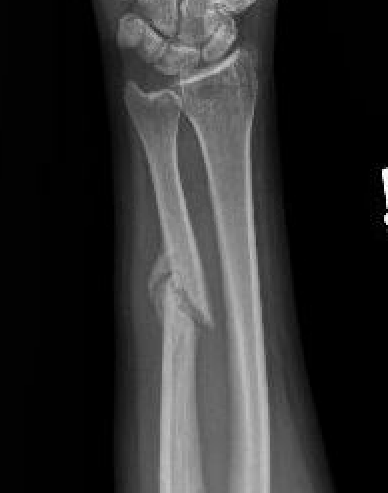

Nonoperative management

Indications

Minimally displaced fractures

- < 50% displaced

- < 10 degrees angulation

Increased nonunion rates with midshaft versus distal fractures

- increased nonunion with midshaft (30%) versus distal 1/3 fractures (2%)